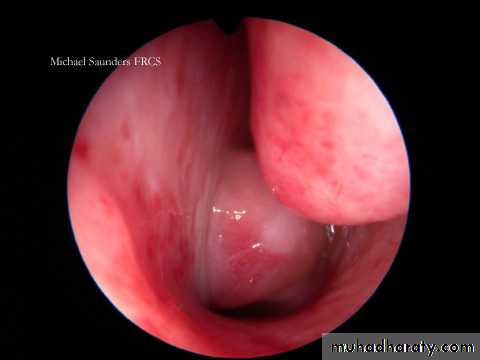

Acute follicular tonsillitis

1. Endoscopy and posterior rhinoscopy: smooth, rubbery lobulated mass in the nasopharynx.